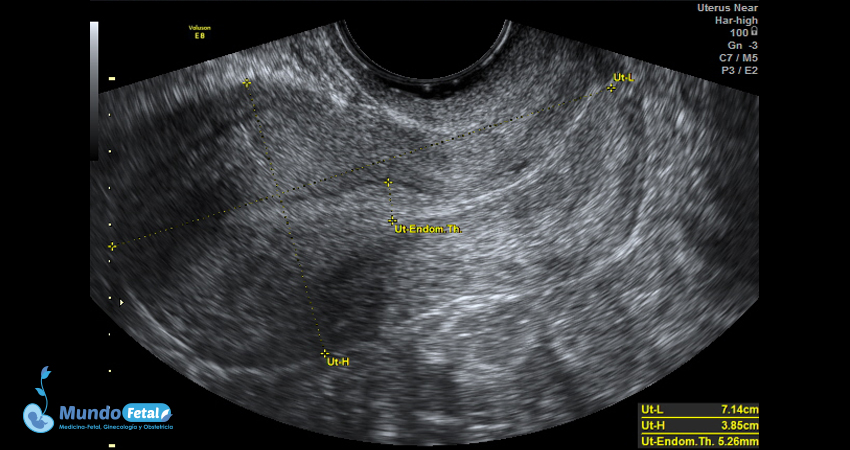

Ultrasonido Pélvico

Estudio anatómico de la región pélvica, que brinda información precisa de (vagina, cérvix, útero, endometrio, trompas de Falopio, ovarios y sus tejidos anexos) de cada uno, descartando alguna complicación de estas estructuras.